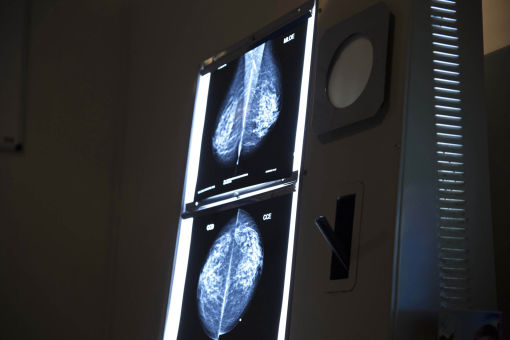

Mamografia bilateral

Mamografia com compressão localizada

Mamografia com magnificação

Biópsia de mama (Core biopsy)

Agulhamento mamário – marcação pré-cirúrgica

Punção por agulha fina de mama (PAAF)

- Trazer peso e altura

- Trazer o último exame de mamografia;

- Não usar creme, desodorante ou similares nas mamas e regiões axilares.